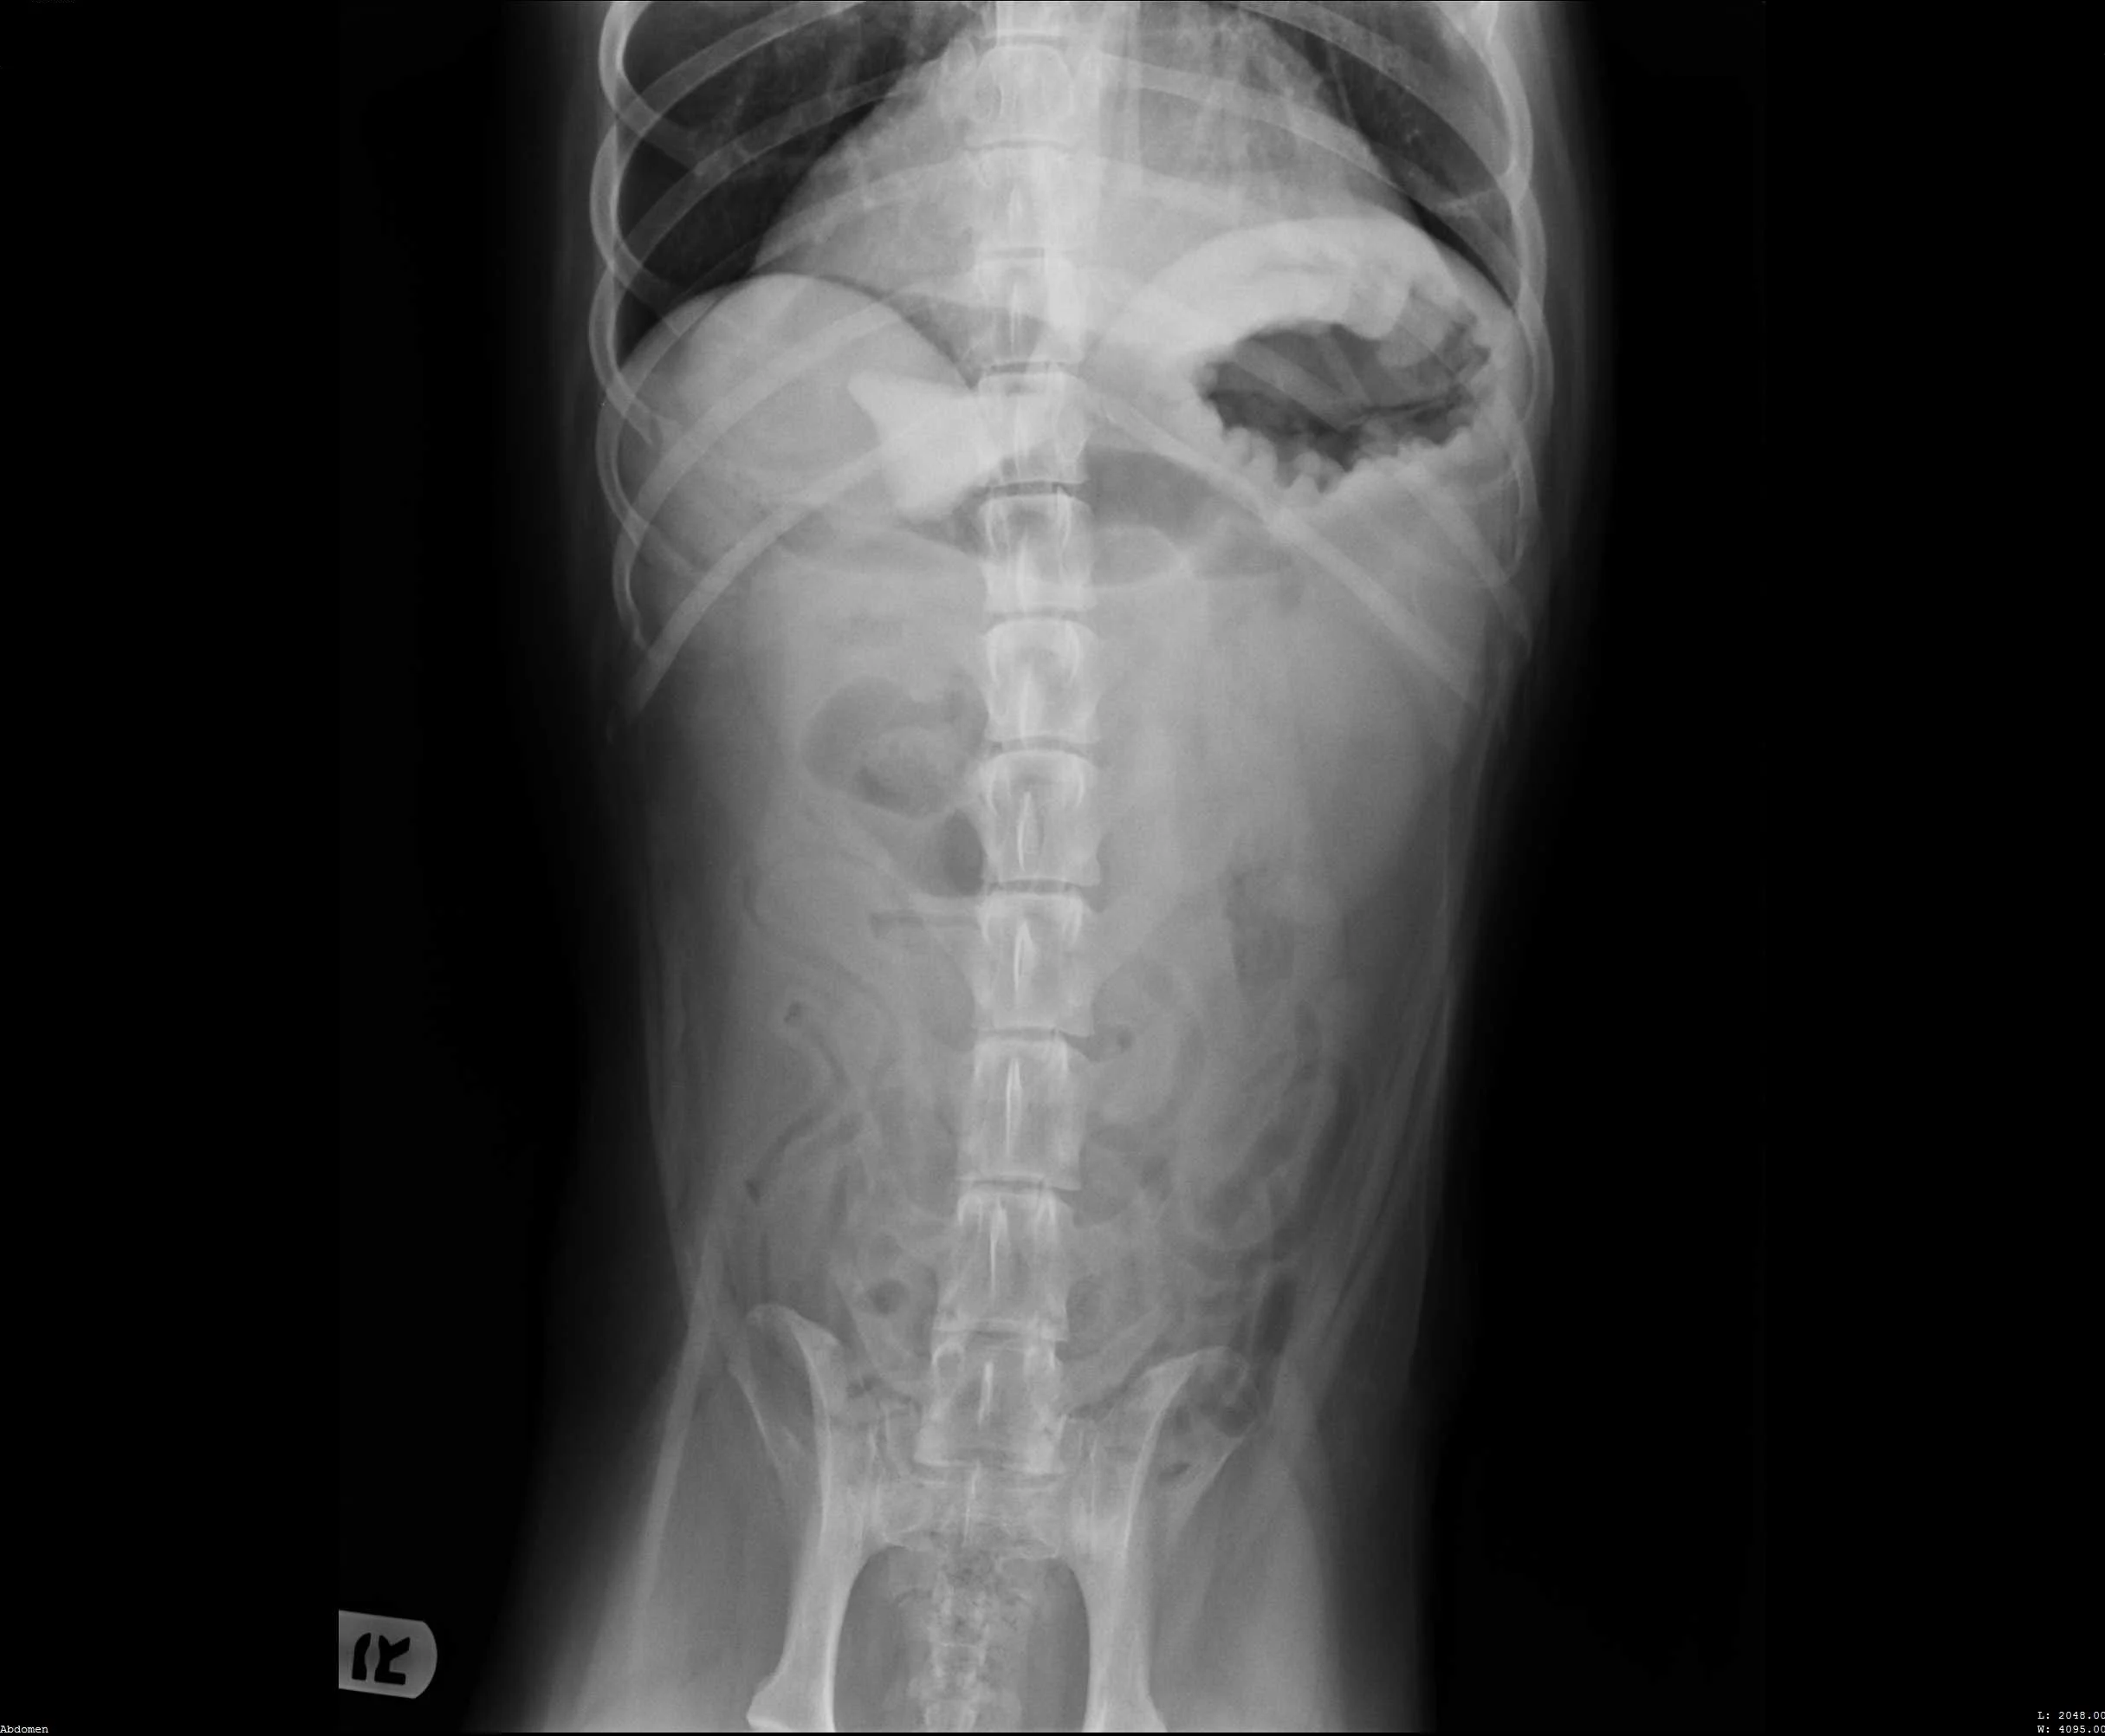

Abdominal radiographs revealed a rock in the patient’s stomach, leading to a diagnosis of a gastric foreign body with outflow obstruction and a secondary finding of megaesophagus.

Right lateral abdomen

Ventrodorsal abdomen